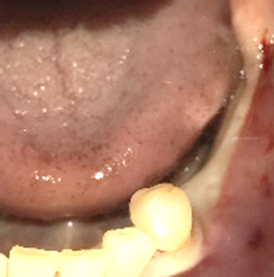

Before

赤丸は抜歯しました

【抜歯後】

【骨造成前】

【骨造成後】

After